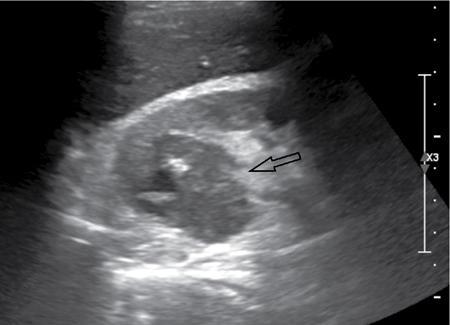

Ultrasound (Fig. 10.12.2.4.2)

Renal abscess, like any other abscess in the body, is a localized collection of infective fluid in the kidney. It is usually a sequela of acute pyelonephritis, and a renal abscess should be suspected when appropriate antibiotic therapy does not lead to clinical response. It can affect all ages and has no recognized gender predilection. Abscess cavities may be either intra- or extraparenchymal. The most common clinical signs or symptoms encountered in renal and perinephric abscesses include fever with or without chills, flank/abdominal pain and dysuria. Renal abscess may be caused by either an ascending infection of the urinary tract or the haematogenous spread of a bacterial pathogen. Severe vasospasm and inflammation in the setting of advanced or inadequately treated cases of acute pyelonephritis may occasionally result in liquefactive necrosis and coalescence of multiple microabcesses to form renal abscess. A perinephric abscess may result from rupture of renal abscess into the perirenal space or direct involvement of perinephric space from inflammatory diseases of pancreas, colon and retroperitoneum. Diabetic patients are predisposed to abscess formation, with 75% of all renal abscesses occurring in this patient population. In addition, these patients can have an insidious presentation because of lack of flank pain related to diabetic neuropathy. Up to 15%–20% of patients with a renal abscess have negative urine cultures reflecting the fact that the infection has been relatively contained within a focal process. Fig. 10.12.2.4.1 summarizes the aetiology and predisposing factors of renal abscesses. In a case of renal and perirenal abscess, plain X-ray abdomen may show renal enlargement, rotation of renal axis, renal displacement, presence of mottled gas in renal areas and loss of psoas outline. The role of IVU in complicated pyelonephritis and renal abscess is rapidly diminished with the advent of superior imaging modalities such as ultrasound and CT scan. IVU generally shows poorly or nonfunctioning kidney with calyceal attenuation and compression due to mass effect. Typically shows a hypoechoic, walled-off collection with internal debris, increased through transmission of sound and no internal colour Doppler signals. Air within is visualized as nondependent echoes with dirty shadowing. However, diagnosis of abscess on sonography is not always straight forward as it can present as echogenic masses. Thus, a contrast-enhanced CT scan becomes essential for diagnosis. Moreover, CT is more sensitive than sonography for assessing spread to the perirenal space. CT is currently the most accurate modality for detection and follow-up of renal abscesses. Two imaging patterns are seen: